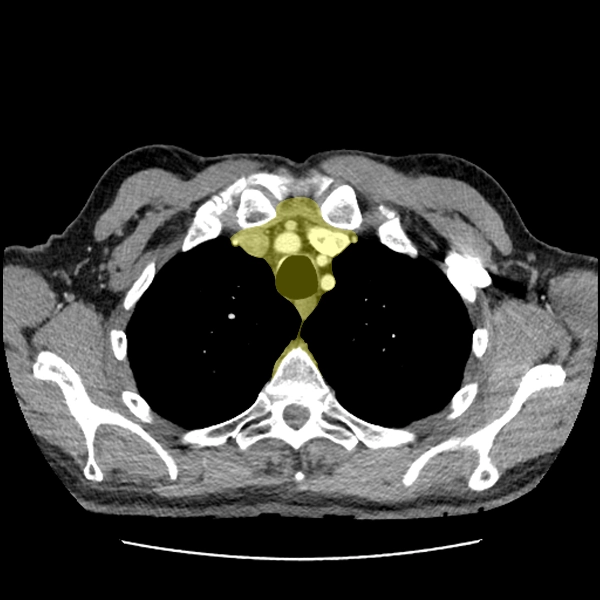

Giải phẫu CT trung thất và mô mềm